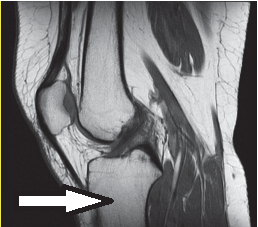

Na rentgenogramie przedstawione jest złamanie Saltera-Harrisa typu

Ilustracja do pytania 37

A. II odcinka bliższego kości piszczelowej.

B. V czwartej kości śródręcza.

C. I ześlizgnięcie bliższej nasady kości udowej lewej.

D. III nasady dalszej kości piszczelowej.